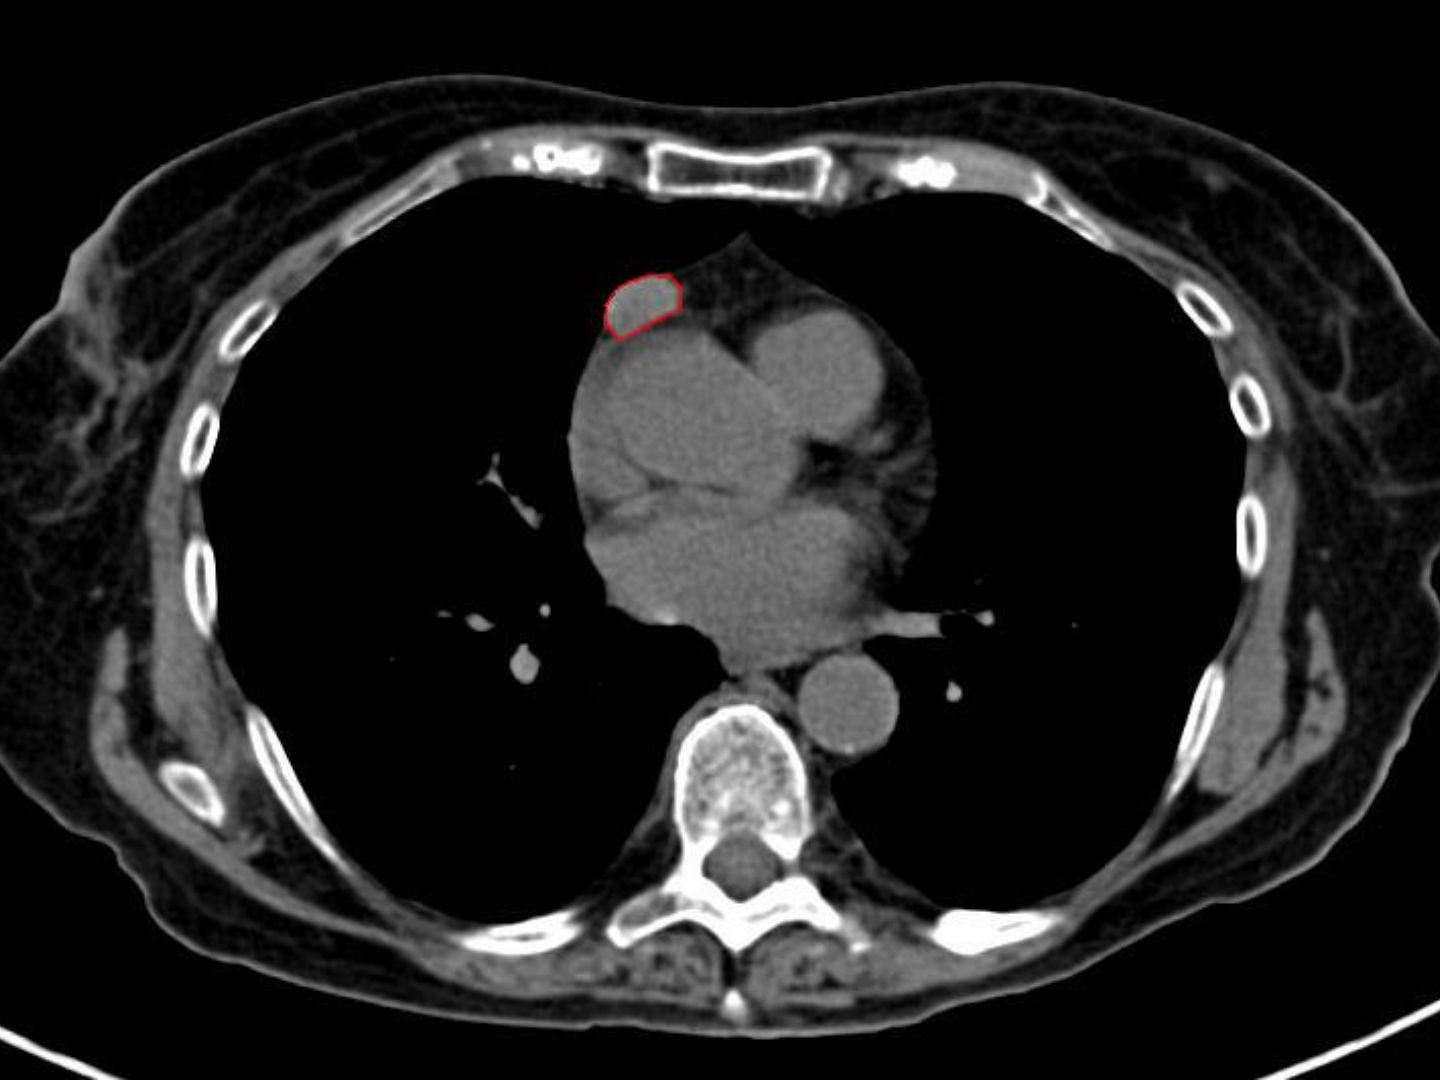

Thymushyperplasie / Thymom nachweisbar

Bei den meisten Patienten kommen (sonst Thymus-untypische) Sekundärfollikel und B-Lymphozyten vor. Vermutlich ist eine Fehlregulation der Sensibilisierung auf den AChR im Thymus verantwortlich.